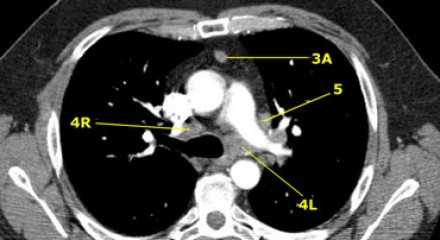

Лимфатические узлы 3 группы не примыкают к трахее в отличии от лимфатических узлов 2 группы. Они подразделюятся на: 3А кпереди от сосудов 3Р позади пищевода/превертебрально Они не доступны при медиастиноскопии. 3Р группа может быть доступна при чреспищеводной эхокардиографии.

На изображении слева 3А узел в преваскулярном пространстве. Обратите внимание так же на ниже расположенные паратрахеальные узлы справа относящиеся к 4R группе.

4L. Левые нижние паратрахеальные лимфатические узлы

4L узлы расположенные слева от левой стенки трахеи, между горизонтальными линиями проведенными касательно верхней стенке дуги аорты и линией проходящей через левый главный бронх на уровне верхнего края верхнедолевого бронха. Они включают паратрахеальные узлы расположенные кнутри от артериальной связки.

Узлы 5 группы (аортопульмонального окна) расположены кнаружи от артериальной связки.

На левом изображении над уровнем легочного ствола представлены нижние паратрахеальные узлы слева и справа, так же здесь представлены узлы 3 и 5 групп.

Изображение слева выше уровня карины. Слева от трахеи 4L узлы. Обратите внимание что они расположены между легочным стволом и аортой, но не в аортопульмональном окне, потому что они лежат медиальнее артериальной связки. Лимфатические узлы латеральнее легочного ствола относятся к 5 группе.